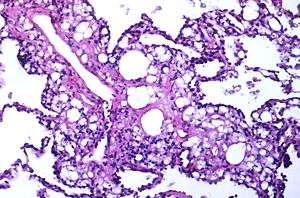

| Numerous interstitial fat globules of varying size accompanied by inflammation and fibrosis is characteristic of chronic lipid pneumonia secondary to lipid aspiration. | |

Once inhaled, these fuels induce an inflammatory reaction in lung tissue. They are not metabolized by tissue enzymes, but undergo emulsification and become engulfed by macrophages which, with time, may disintegrate and release oily substances surrounded by fibrous tissue and giant cells.[5]